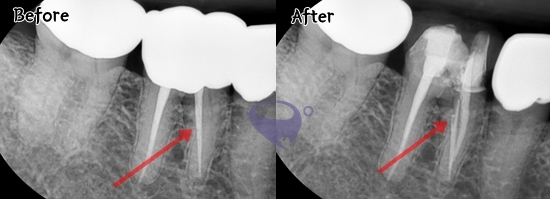

#患者 一 #再神经手术 找别的 #根管

- 49需要重新接受根管治疗的情况!! 这位患者右边下面牙齿接受根管治疗也是吃东西时还是疼内院我们牙科。 根管治疗是‘除去牙齿神经管内的神经或者血管一样的软组织然后消毒密闭防止感染的治疗方式’ 接受治疗也已经四五年了。我们先拍放射线照片。 牙齿解剖结构上神经管是太细而且复杂的。少有的神经管中一个没有治疗的情况也有。所以我们重新治疗根管治疗。 除去本牙齿的补牙物重新接受根管治疗的放射线照片。 第一张照片上看不到的神经管找到了治疗的情况我们可以看得到。 根管治疗以后这位患者吃东西时有的症状得到改善。 - - Park Avenue 牙科诊所提供来自纽约的最好的种植体治疗与先进的医疗实践,以帮助您找到完美的微笑。 - 与ParkAvenue 牙科诊所一起,恢复您一直希望的自信微笑! - ⏰诊疗时间⏰ 平日 上午09:30-下午18:30 周六 上午09:30-下午16:00 周日,国家节假日休 午餐时间 下午13:00-14:00 - - 🏙地址 Petra栋 2,3楼65 9 驿三洞,江南区,大韩民国 135-080 📞联系方式 电话 (02)566-6628 正畸科 (02)564-2885 QQ 2787131397 微信 Parkavedc . . #牙科医生 #韩国牙科 #牙齿美白 #牙齿矫正 #牙齿美容 #牙齿不整齐 #치아미백#parkavenue #parkavenuedentalclinic#parkavenuedental#parkavenuedental_seoul #parkavenue牙科 #牙齿疼 #牙疼 #牙齿美白 #牙齿白不白 #牙齿黄 #牙齿很白 #韩国口腔医院 #江南牙科